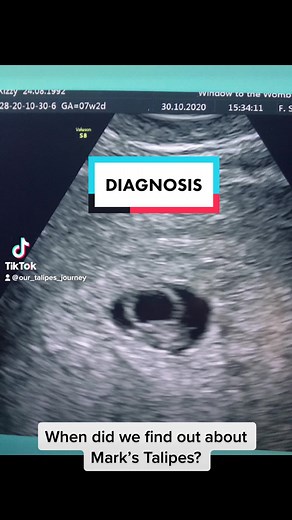

our_talipes_journey

Our Talipes Journey on TikTok

Our Talipes Journey(@our_talipes_journey). This - Megan McKenna. I have had loads of questions about Mark’s diagnosis so here is the journey at the beginning 🥰 a scary time and not a lot of info available which is why we are sharing ️ #talipesbaby #talipesjourney #talipesequinovarus #talipescute #talipeswarrior #talipes #clubfootjourney ...